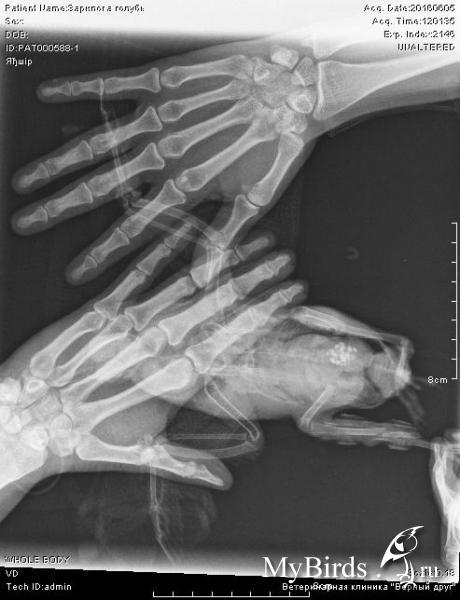

olinca Опубликовано 5 июня, 2016 Автор #16 Опубликовано 5 июня, 2016 (изменено) Меня беспокоит эта агломерация белых точек, это не раздавленное яйцо? Ну и кости на фронтальной проекции видно, что разошлись довольно сильно На рентгене довольно хорошо видно шину Шина состоит из 2-х зубочисток, одну, сбоку лапы особенно хорошо видно, а вот вторая лишь чуть чуть выставляется и идёт ЗА костью. Надеюсь, не сильно мешает обзору. Изменено 5 июня, 2016 пользователем olinca

KamaRo Опубликовано 5 июня, 2016 #17 Опубликовано 5 июня, 2016 olinca, напишите Зосе, на втором фото мне видится перелом с сильным смещением (на первом фото как то не понятно). нужно было снять шину для рентгена.

olinca Опубликовано 5 июня, 2016 Автор #18 Опубликовано 5 июня, 2016 Первые 2 фото - это увеличенные фрагменты рентгена (вторые 2 фото). Само первое - боковая проекция, на ней действительно плохо видно, второе - фронтальная.